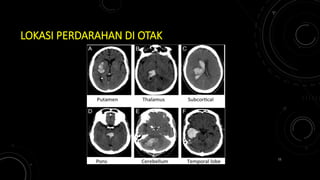

LOKASI PERDARAHAN DI OTAK

Mark S. Greenberg. Handbook of Neurosurgery 8th Edition. Thieme. 2016